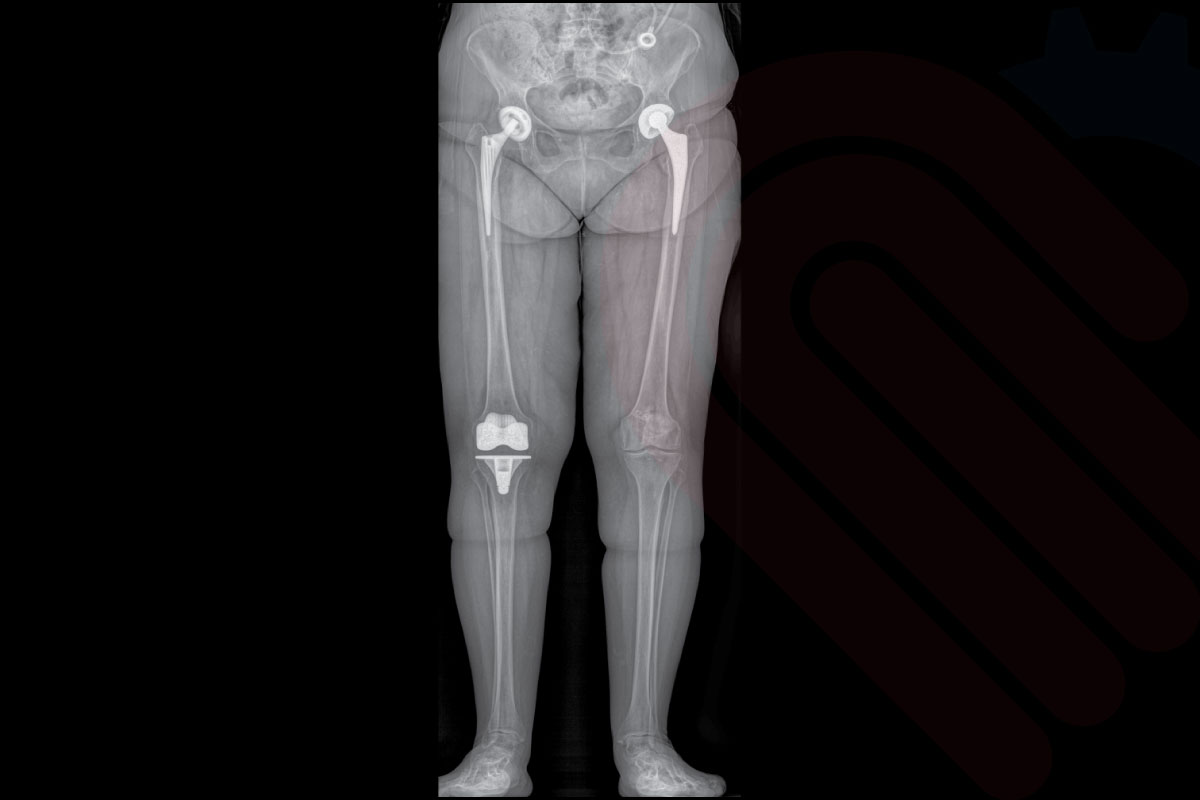

kneeEOS, EOSedge sistemi ile elde edilen düşük doz, gerçek boyutlu biplanar görüntülerden faydalanarak alt ekstremite hizalanmasının 3D analizini ve cerrahi planlamasını yapan özel bir yazılımdır. Total diz protezi (TKA) ve diğer diz rekonstrüksiyon cerrahilerinde, mekanik eksen hizalaması, kemik kesim açıları ve implant boyutlandırması gibi kritik parametreleri preoperatif olarak belirlemenizi sağlar. Hastanın yük taşıyan pozisyonda çekilmiş görüntüleri sayesinde, planlamalar fizyolojik yük koşullarına uygun şekilde yapılır. Klinik araştırmalar, kneeEOS ile yapılan planlamaların, cerrahi sonrası mekanik eksen doğruluğunu ve implant yerleşim hassasiyetini anlamlı ölçüde artırdığını ortaya koymuştur*.

Klinik Destek

• Parratte et al., The Journal of Arthroplasty, 2018

• → kneeEOS planlaması ile yapılan TKA cerrahilerinde, postoperatif mekanik eksen hizalanması doğruluğu anlamlı derecede artmıştır.